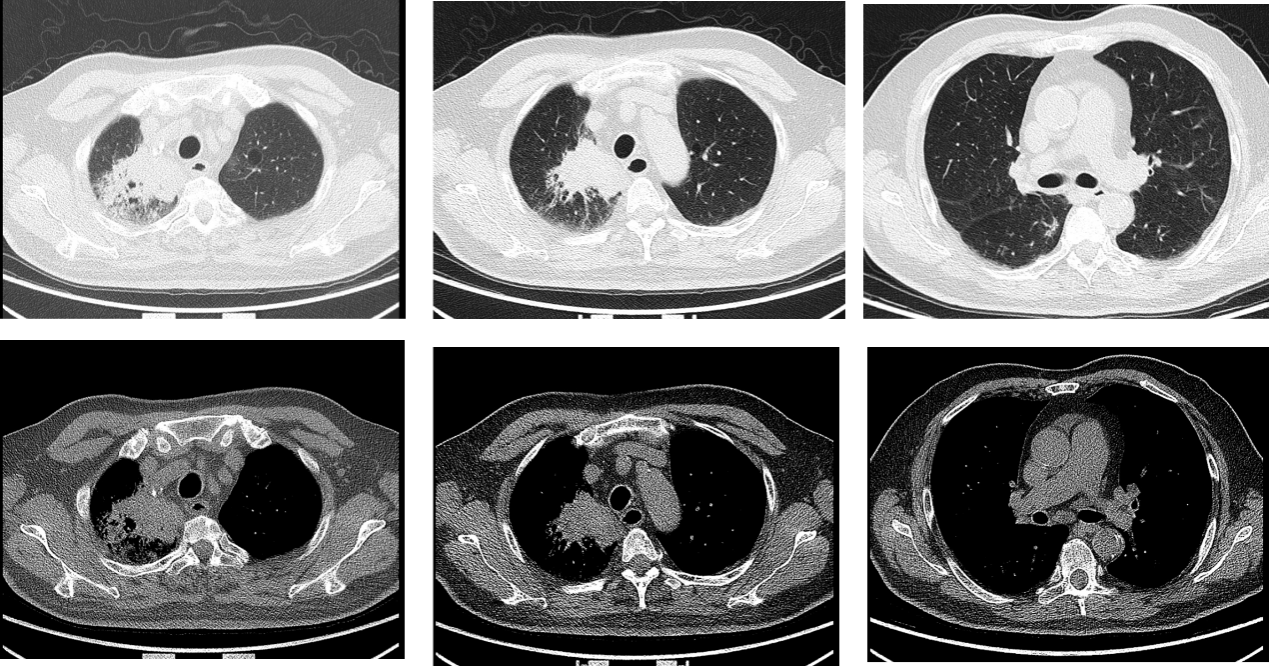

2025-02,待患者呼吸道症状缓解,开始第一程舒格利单抗+白蛋白紫杉醇+卡铂方案,总计治疗6疗程,期间患者耐受性良好。2025-06,复查胸部CT提示病灶明显缩小,喉镜提示未见新生物。

图6. 2025-06疗效评估

2025-06,复查PET-CT,对比2025-01-20。

PET/CT:

• 1. 喉癌治疗后,喉壁未见增厚,糖代谢未见异常。

• 2. 右肺癌治疗后,原右肺数个高代谢团块现已消失;右肺上叶少量类结节、条索灶,糖代谢未见异常,考虑肿瘤代谢完全缓解可能,请结合临床。

• 3. 双肺各叶胸膜下多发细小结节,糖代谢未见异常,考虑炎性病变可能。左肺上叶肺大泡。双肺门及纵隔(4R4L、7组)多发小淋巴结,糖代谢未见增高,考虑炎性增生可能。双侧胸膜增厚;心包少量积液。

图7. 2025-06疗效评估

影像科:2025-03CT示右肺病灶缩小,疗效评价为PR。6程化疗后复查PET/CT仍存在小结节,在实体瘤的疗效评价中,只能判断为PR。但是PET/CT提示病灶糖代谢未见异常,而且CT无强化,可以考虑为坏死,但此时仍不能确定为CR。